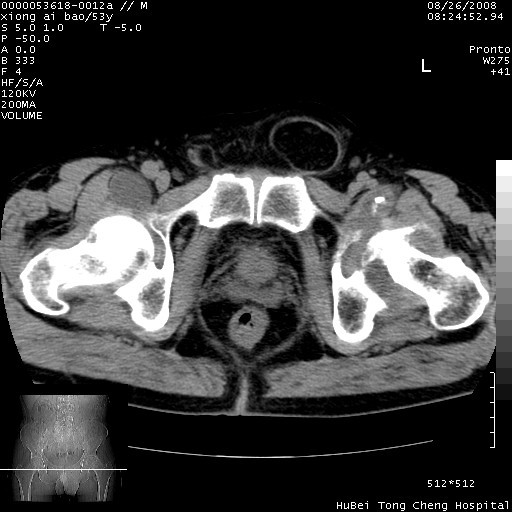

标题: CT15583:M,53Y。请老师指教分析骨盆及其他病变。 [打印本页]

标题: CT15583:M,53Y。请老师指教分析骨盆及其他病变。

股骨头坏死/腹股沟疝。

双侧股骨头无菌坏死,左侧腹股沟斜疝。

非常典型病例,双侧股骨头坏死伴双髋关节周围软组织肿胀,左腹股沟疝。

双侧股骨头坏死伴双髋关节周围软组织肿胀,左腹股沟疝。

双侧骨股头无菌性坏死,左侧腹股沟疝

双侧髋关节肿胀明显,感觉还不能排除结核。

考虑双侧髋关节结核,左侧腹股沟疝